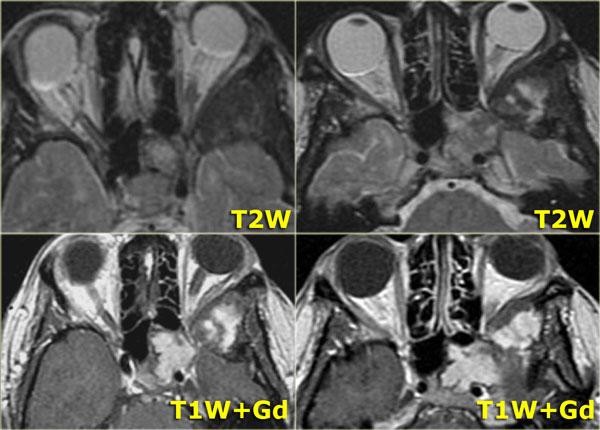

Khi muốn phân biệt dịch tiết cô đặc với khối u tân sinh, điều quan trọng là phải có hình ảnh trước và sau tiêm thuốc tương phản từ.

Nếu chỉ nhìn vào hình sau tiêm thuốc ở bên phải, bạn có thể bị nhầm lẫn khi cho rằng có sự ngấm thuốc đồng nhất của khối trong hốc mũi (dấu hoa thị) cũng như trong xoang sàng và xoang hàm bên phải.

Tuy nhiên, khi nhìn vào hình trước tiêm thuốc, bạn sẽ nhận thấy rằng nội dung trong xoang sàng và xoang hàm tăng tín hiệu so với khối trong hốc mũi (vùng khe mũi giữa), vì các xoang này chứa đầy dịch tiết cô đặc.

Khối ngấm thuốc đồng nhất này phải được coi là khối u cho đến khi được chứng minh ngược lại.

Các dấu hiệu hình ảnh không đặc hiệu và chẩn đoán phân biệt bao gồm polyp hoặc ung thư biểu mô.

Sinh thiết xác nhận là u nhú đảo ngược.

U nhú đảo ngược (2)

Bên trái là một bệnh nhân khác nhập viện vì nghẹt mũi.

Hãy nghiên cứu các hình ảnh bên trái.

Tự mình xác định xem bạn đang quan sát một khối đặc, dịch tiết cô đặc, sự kết hợp của cả hai, hay một thứ gì đó hoàn toàn khác.

Hình T1W trước tiêm thuốc cho thấy một vùng tăng tín hiệu trong xoang hàm, tương ứng với chất dịch giàu protein.

Phía trong của vùng đó là một vùng giảm tín hiệu tương tự tín hiệu của nhãn cầu (có thể là dạng nang).

Phần lớn mô mềm trong xoang hàm phải tương đối giảm tín hiệu trên hình T1W trước tiêm thuốc,

nhưng ngấm thuốc đồng nhất, gợi ý khối u.

Hình T2W bên trái xác nhận thành phần dạng nang (mũi tên vàng).

Hình CT mặt phẳng coronal minh họa rõ nét hình ảnh tái cấu trúc xương và giãn nở (đầu mũi tên).

Kết quả giải phẫu bệnh xác nhận là u nhú đảo ngược.

Vị trí tổn thương khá điển hình.